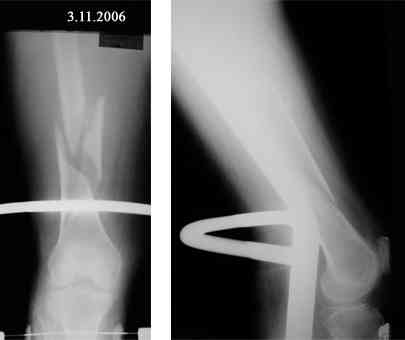

В продолжение темы оскольчатого перелома бедренной кости.

Р-граммы в динамике